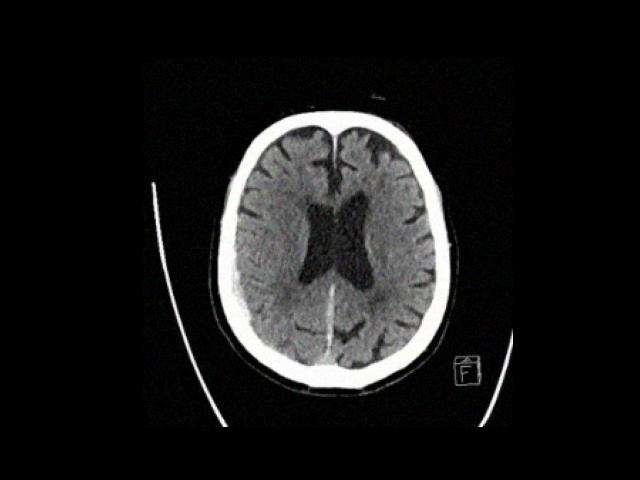

Sample Gallery